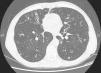

We report the case of a 64-year-old man, health worker, with no significant personal history or known toxic habits, who reported a 3-year history of non-productive cough, with no particular diurnal pattern, dysphonia and excess mucosity in the oropharyneal cavity, and additionally, in the last year, asthenia and recurrent episodes of low-grade fever. Forced spirometry results were as follows: FEV1/FVC 0.46; FEV1 1.91L (60%); FVC 4.14L (101%). Bronchodilator challenge and skin prick tests with allergens were negative. Computed tomography of paranasal sinuses, sweat chloride test, IgG, IgM, IgA, IgE and alpha-1 antitrypsin levels were all within normal ranges. A human immunodeficiency virus test was negative. A barium swallow study of gastroesophageal transit revealed gastric reflux. Chest CT showed bronchiectasis in the middle lobe and lingula associated with mucus plugs and distal centrilobular nodes (Fig. 1). Macroscopic results from fiberoptic bronchoscopy sampling were normal, while M. avium complex was isolated from bronchoalveolar lavage. The patient met diagnostic criteria for environmental mycobacteria published by the American Thoracic Society (2007)3 and was diagnosed as having MAC infection consistent with LWS.